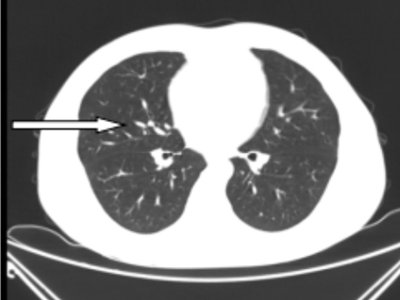

41岁的彭先生,2022年3月份出现咳嗽咳痰,多家医院治疗效果不佳,外院查胸部CT提示肺部占位及大量胸水,且外周血白细胞明显升高及颈部多发的淋巴结肿大。4月初疑诊结核收入香港马会app结核科,入院后发现浅表淋巴结进行性增大,经血液科会诊,考虑淋巴瘤并骨髓侵犯。患者转入血液内科后,行骨髓涂片提示有77%肿瘤细胞,同时请耳鼻喉科行颈部淋巴结切除病检,最终确诊为低级别滤泡性淋巴瘤并肺部、骨髓侵犯(IV期,EZH2基因突变阴性)。4月27日根据最新的滤泡性淋巴瘤诊治指南(NCCN指南及CSCO指南),选用GB方案(奥妥珠单抗联合苯达莫司汀)化疗。第一周期化疗后,彭先生状态良好。5月26日复查肺部CT,肺部占位、胸水及淋巴结明显缩小。咳嗽及气促也完全消失。目前,患者仍在血液内科接受后续治疗。

图二:5月26日第一次化疗后肺部CT,箭头所指的肺实变已消失